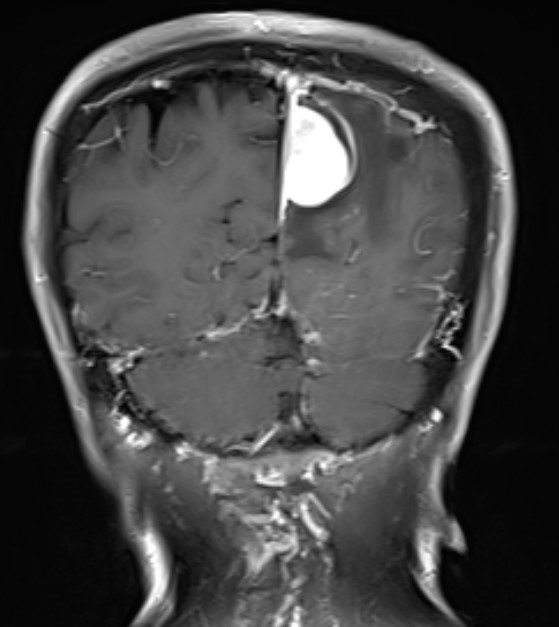

头部MR检查提示:左顶枕镰旁脑膜瘤

术后MR复查提示肿瘤切除干净